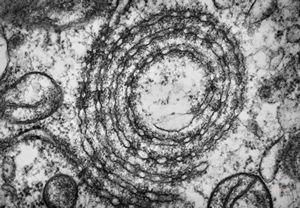

M,3y. | mast cell - granules with scroll-like formations - n. suralis, Krabbe globoid leukodystrophy

F,23y. | mast cell - granules with scroll-like formations - n. suralis, demyelinating neuropathy

F,31y. | mast cell - granules with scroll-like formations - n. suralis, demyelinating neuropathy

M,12y. | mast cell - granules with scroll-like formations - skin, urticaria pigmentosa